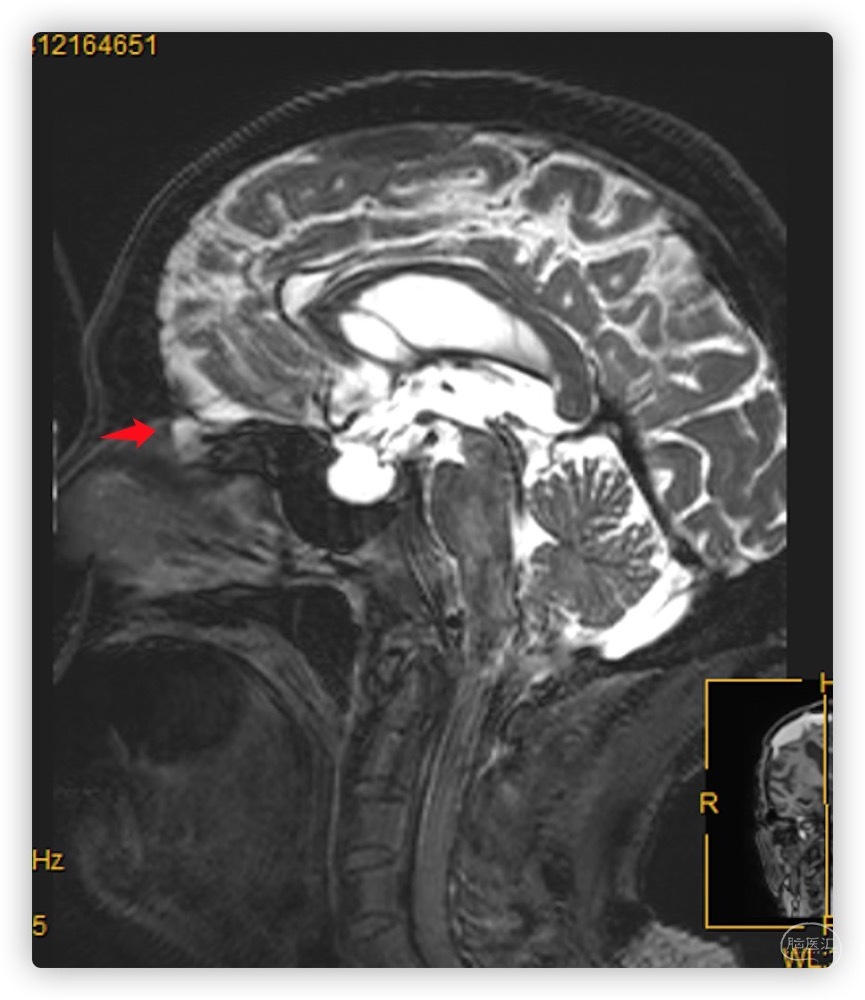

进一步头颅MRI检查查找脑脊液漏原因,可见前颅底筛凹处脑脊液漏出。